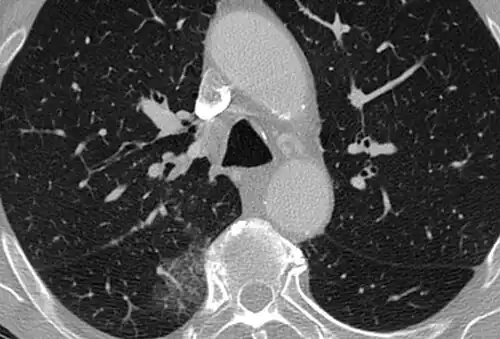

CT image showing patchy areas of ground-glass opacities representing pulmonary edema.

The diffuse pattern typically refers to GGOs in multiple lobes of one or both lungs. Broadly, a diffuse pattern of GGO can be caused by displacement of air with fluid, inflammatory debris, or fibrosis. Cardiogenic pulmonary edema and ARDS are common causes of a fluid-filled lung. Diffuse alveolar hemorrhage is a rarer cause of diffuse GGO seen in some types of vasculitis, autoimmune conditions, and bleeding disorders.[6]